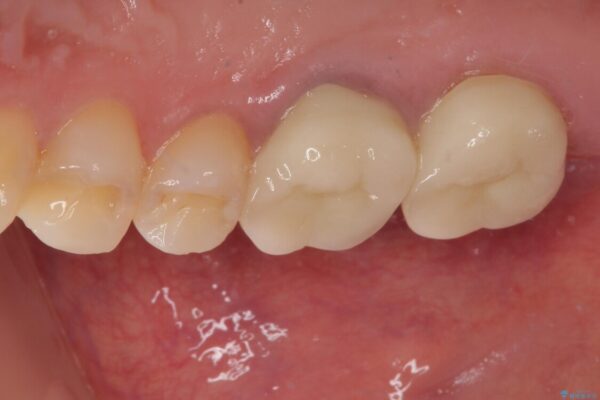

その後、挺出していた右上第一大臼歯と第二大臼歯に装着されていた銀歯についても、審美性と適合性の向上を目的に、オールセラミッククラウンにやり替えました。

これにより、より自然で美しい見た目と、高い精度の咬合が得られています。

治療後

• 挺出歯を圧下してスペースを確保!目立たない部分矯正で下顎大臼歯にインプラント治療を実現 治療後画像